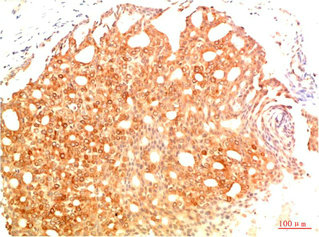

• Immunohistochemical analysis of paraffin-embedded Human Colon Carcinoma Tissue using Acetyl P53(K382) Mouse mAb diluted at 1:200.

• Immunohistochemical analysis of paraffin-embedded Human Breast Carcinoma Tissue using Acetyl P53(K382) Mouse mAb diluted at 1:200.